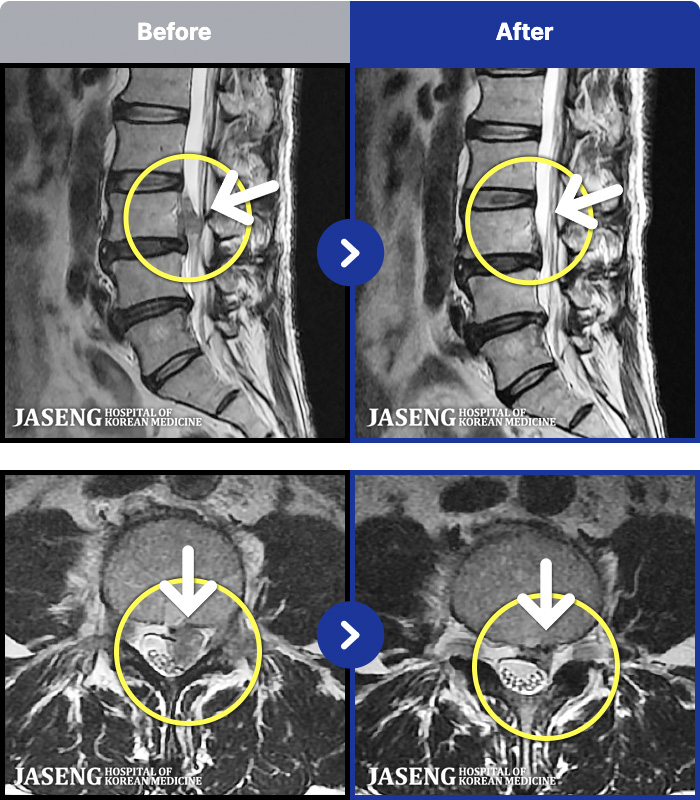

[ϻ] 24.07.25~25.08.01

ȯںп Ǹ ǿ ԿǾ, ο ġ ۿ Ƿ ġḦ Ͻñ ٶϴ.